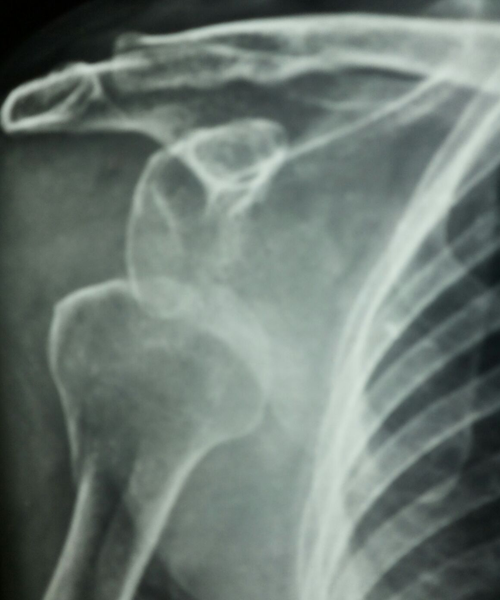

Case:1 Fracture Dislocation Upper end Humerus

Pre-op AP

Pre-op Lateral